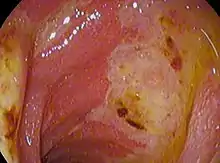

An esophagogastroduodenoscopy (EGD), a form of endoscopy, also known as a gastroscopy, is carried out on people in whom a peptic ulcer is suspected. It is also the gold standard of diagnosis for peptic ulcer disease.[14] By direct visual identification, the location and severity of an ulcer can be described. Moreover, if no ulcer is present, EGD can often provide an alternative diagnosis.

Gastric ulcers are most often localized on the lesser curvature of the stomach. The ulcer is a round to oval parietal defect ("hole"), 2–4 cm diameter, with a smooth base and perpendicular borders. These borders are not elevated or irregular in the acute form of peptic ulcer, and regular but with elevated borders and inflammatory surrounding in the chronic form. In the ulcerative form of gastric cancer, the borders are irregular. Surrounding mucosa may present radial folds, as a consequence of the parietal scarring.